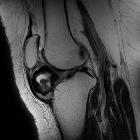

MRI

Features include

-

T1

- mass in the Hoffa fat pad

- generally low signal

- isointense to muscle

- some dark areas signifying calcification

- T2: high signal in the cartilaginous components

- PD: as above with T1, plus high intensity signal areas corresponding to medullary bone

- GRE: prominent signal voids within a nodular mass